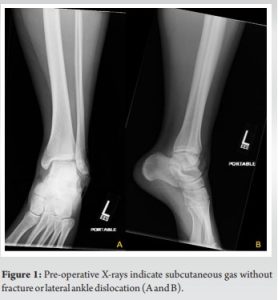

A 22-year-old female presented to the emergency department due to an ankle injury suffered while playing volleyball. The injury occurred on impact from a jump resulting in a sudden varus force and inversion injury to the ankle. This resulted in a 7 × 5 cm open wound overlying the lateral malleolus with exposed bone. On presentation, there was extrusion of the distal fibula through her skin with invagination of skin distal to the tip of the fibula. The patient was neurovascularly intact. An x-ray obtained at an outside hospital showed no acute fracture or dislocation of the ankle joint. The ankle mortise was well preserved on initial imaging (Fig. 1). The patient presented to our institution on the day of the injury and was subsequently taken urgently to the operating room. Antibiotics were initiated before transfer to our institution and preoperatively.